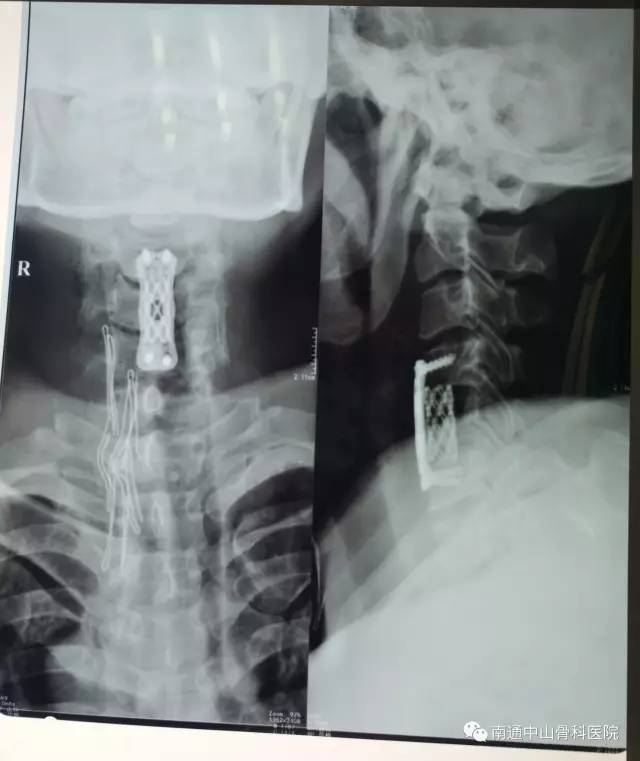

我院胡院长了解了患者的病情后,立即组织相关人员对他的病情进行分析、会诊,认为必须尽快对患者进行“颈前路颈椎间盘摘除+颈5椎体次全切除椎管减压、钛网植骨融合、钢板螺钉内固定手术”,因颈椎手术是一项高风险手术,手术中,手法操作不能有丝毫的偏差。

2017年5月27日,由于术前准备充分,方案科学合理,3个多小时的手术进行的非常顺利。陈先生安全回到病房里。术后即有详细的护理方案继续加强治疗。经过不到一周的治疗,陈先生已能够自主举起双臂,目前正在恢复中,再过几天就能出院了。